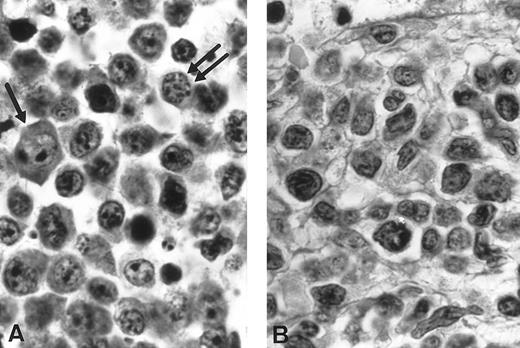

Morphological studies of pathologicals specimens. (A) Imprint of the three cases of NK-NHL. Case no. 1: Large blastic lymphoid cells looked like immunoblasts with a high mitotic rate (MGG, original magnification × 3,300). Case no. 2: Medium lymphoid cells with irregular nuclei and fine chromatin (MGG, original magnification × 3,300). Case no. 3: Medium and large lymphoid cells with vacuoles and azurophilic granules in the cytoplasm (MGG, original magnification × 3,300). (B) Immunophenotypic analysis. Coexpression study of CD3 and CD56 in the three cases found the unique tumoral phenotype CD3− CD56+. Heterogeneity is described concerning CD4 and CD8 expression. Case no. 1: CD4−CD8+; Case no. 2: CD4+CD8−; Case no. 3: CD4−CD8−.

In the first case, the imprint from a lymphadenopathy was mainly composed of large blastic lymphoid cells. The cytoplasm was abundant and slightly basophilic but without cytoplasmic granules. The nucleus was sometimes irregular with a single centrally located nucleolus. These blast cells looked like immunoblasts. Acid phosphatase polar positivity was observed in 100% of the blasts. Mitoses figures were frequent (Fig 1A). Histopathologic study of a voluminous lymph-node showed a diffuse infiltrate by medium to large cells with a basophilic cytoplasm, round nucleus containing medium and sometimes large nucleoli. Some medium-sized cells realized a plasmacytoid pattern (Fig 2A). A reappraisal of the ileal initial resection discovered similar cells infiltrating the mucosae between the glands and some in the epithelium between the cells.

In the second case, bone marrow aspiration showed an infiltrate of medium-sized lymphoid cells with fine chromatin. The blast cells contained irregular nuclei, usually with some indentations. The nucleoli were slightly apparent (Fig 1A). Acid phosphatase was negative. On bone marrow biopsy, a diffuse interstitial infiltrate with focal reinforcements was seen associated with a systematized myelofibrosis (Fig 2B). The cells were medium and large with slightly basophilic cytoplasm.

In the third case, the cervical lymph node imprints showed medium and large lymphoid cells. The nuclei exhibited a finely clumped chromatin. The basophilic cytoplasm was relatively abundant with some vacuoles and small azurophilic granules. Mitoses were frequently observed (Fig 1A). Histopathologic study of the lymph node showed a diffuse infiltrate with a starry sky pattern caused by numerous disseminated histiocytes with tingible bodies (Fig 3A). The lymphomatous cells were medium sized, with either an irregular or a more round nucleus with a basophilic cytoplasm. The lymphoma was classified as a high grade pleomorphic T-cell malignant lymphoma with large cell predominance. (Fig 3B). The bone marrow biopsy disclosed a diffuse massive infiltrate constituted by the same cells without myelofibrosis.